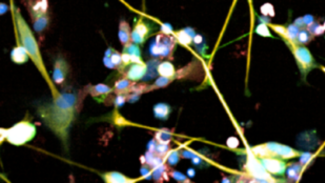

εγκεφάλου

22:14 | 20/09/2024

Σε μιας μεγάλης κλίμακας έρευνα φαρμάκων εντοπίστηκε ότι ένα εγκεκριμένο φάρμακο, η βορτιοξετίνη, που χρησιμοποιείται για τη θεραπεία της κατάθλιψης, φαίνεται να αποτελεί έναν από τους πιο αποτελεσματικούς παράγοντες κατά του γλοιοβλαστώματος, ενός επιθετικού και θανατηφόρου τύπου καρκίνου του εγκεφάλου. Η έρευνα δημοσιεύθηκε στο περιοδικό «Nature Medicine».